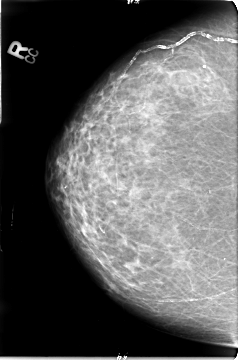

B_3027_1.RIGHT_CC

LEFT_CC LINES 4720 PIXELS_PER_LINE 3128 BITS_PER_PIXEL 12 RESOLUTION 50 OVERLAY

RIGHT_CC LINES 4680 PIXELS_PER_LINE 3112 BITS_PER_PIXEL 12 RESOLUTION 50 NON_OVERLAY

FILE: B_3027_1.LEFT_CC.OVERLAY

TOTAL_ABNORMALITIES 2

ABNORMALITY 1

LESION_TYPE MASS SHAPE IRREGULAR MARGINS ILL_DEFINED

ASSESSMENT 4

SUBTLETY 4

PATHOLOGY MALIGNANT

TOTAL_OUTLINES 1

BOUNDARY

ABNORMALITY 2

LESION_TYPE CALCIFICATION TYPE PLEOMORPHIC DISTRIBUTION CLUSTERED